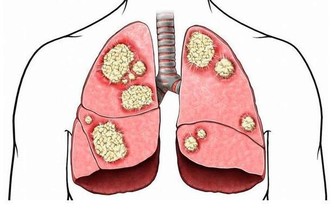

人到了一定歲數,或者終年食用高脂肪飲食,血管內膜增厚,就會構成“斑塊”,易致使動脈狹窄,特別是血管分支入口,血流艱難,易發作阻塞。

你的動脈阻塞缺血嗎?

一個很明顯的信號能夠驗證,人的足部有一個明顯能摸到脈息的方位,即是足背正中最高點,輕摸能感遭到脈動。假如是輕度下肢動脈阻塞的人來說,能摸到足部脈息,證實動脈血一向通到足背部。可走了一段路後,再摸,就摸不到脈息了,這時,很可能發作了動脈血管阻塞。

自查血管阻塞辦法

把腳舉高,45度,2分鐘,仔細觀察兩條腿。假如一條腿呈蒼白,乃至是蠟白,腿部肌膚出現透明狀,待腿拿下來後,康復正常坐姿,假如這條腿出現微紅,這就闡明這條腿現已缺血了。